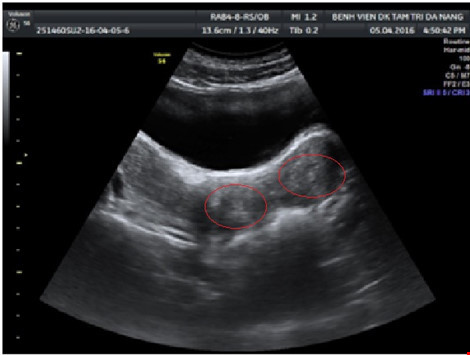

Trường hợp đầu tiên là bệnh nhân nữ 24 tuổi, chưa lập gia đình, nhập viện trong tình trạng đau hố chậu phải dữ dội, kèm buồn nôn. Qua khám lâm sàng và siêu âm ổ bụng - phần phụ, bác sĩ phát hiện xoắn phần phụ phải, bao gồm nang nước cạnh vòi trứng, vòi trứng và buồng trứng phải. Bệnh nhân được mổ nội soi cấp cứu tháo xoắn, bóc nang, bảo tồn toàn bộ vòi trứng và buồng trứng phải. Sau mổ, bệnh nhân hồi phục ổn định.

Trường hợp thứ 2 là một bệnh nhân nam 50 tuổi, vào viện vì đau bìu trái cấp tính, được chẩn đoán xoắn tinh hoàn trái sau thăm khám lâm sàng và siêu âm Doppler. Ê-kíp phẫu thuật của bệnh viện đã mổ tháo xoắn tinh hoàn, thừng tinh, khâu phục hồi mô tinh hoàn, bảo tồn thành công cơ quan sinh dục. Bệnh nhân hiện phục hồi tốt, không có dấu hiệu hoại tử.